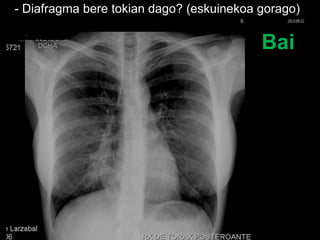

- Diafragma bere tokian dago? (eskuinekoa gorago)

Bai